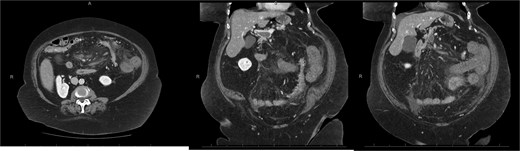

A 45-year-old male presenting with a 10-day history of isolated right lower quadrant (RLQ) abdominal pain. His history included deep vein thrombosis, coronary artery disease with prior STEMI, left anterior descending artery stenting in 2014, and ongoing antiplatelet therapy with aspirin. Upon admission, RLG tenderness was noted. Laboratory revealed leucocytosis (WBC 16 G/L) and elevated CRP (70 mg/L). E-CT revealed superior mesenteric and portal systems thrombosis with ischemia of a small bowel loop in the RLQ, characterized by absent bowel wall enhancement and free fluid (Fig. 4). Besides these findings, he was managed conservatively with a UFH bolus of 5000 U/l, followed by a continuous infusion of 36 000 U/l over 24 h (target INR 0. 35–0. 7), Ceftriaxone and Metronidazole, bowel rest, and ICU monitoring for 48 h. Clinical and biological improvement was rapid. E-CT on the second day showed no signs of perforation (Fig. 5). He was discharged after 7 days on LMWH (enoxaparin sodium 90 mg every 12 h). Twenty days later, he re-presented with acute RLQ pain and localized peritonism. E-CT revealed a covered perforation of the previously ischemic small bowel loop (Fig. 6). A segmental bowel resection with primary anastomosis was performed by laparotomy (Fig. 7). The postoperative course was uneventful, and he was discharged on postoperative day 4 with sodium enoxaparin 90 mg/12 h.

E-CT in the second patient at admission. White arrows showing porto-mesenteric thrombosis. Dashed arrows indicate a portion of small bowel loop ischemia in the right lower quadrant characterized by the absence of bowel wall enhancement and free fluid.